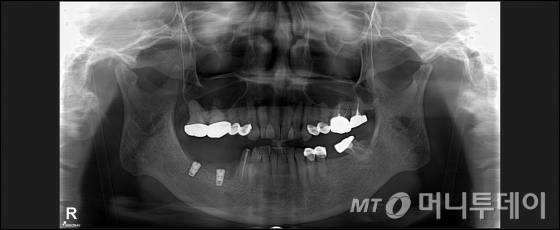

# 20년간 부분틀니를 사용한 A씨(52)는 임플란트를 하기 위해 대학병원을 찾았다가 잇몸이 약해 골이식이 필요하다는 진단을 받았다. 골이식 후 임플란트 2개를 식립하고 크라운(보철물) 3개를 연결해 씌우는 브리지 수술을 하는 데 총비용이 600만원 들 것으로 예상됐다. 가격에 부담을 느낀 A씨는 다른 치과의원에서 같은 치료를 받는 데 반값이면 가능하다는 얘기를 듣고 바로 임플란트를 식립했다. 하지만 한 달 후 A씨는 대학병원을 다시 찾아야 했다. 임플란트를 식립한 곳이 계속 아프고 냄새가 났기 때문이다. 골이식을 제대로 하지 않아 감염 증상과 신경관 손상이 발생한 것이었다. A씨는 결국 앞서 식립한 임플란트를 모두 제거하고 골이식을 한 후 임플란트 수술을 다시 받았다. 애초 7개월이면 가능했던 치료는 1년6개월 만에 끝났다.

비스포스포네이트계의 골다공증약을 오래 복용한 환자의 경우 턱뼈에 골수염이 발생할 확률이 높아 주의해야 한다. 임플란트 시술로 염증이 번질 경우 턱뼈를 잘라내야 할 수도 있어서다. 허민석 서울대치과병원 영상치의학과 교수는 “골다공증약을 오래 복용했다면 CT(컴퓨터단층촬영)나 파노라마 영상 등을 촬영한 후 반드시 전문가의 판독을 거쳐 임플란트 시술 여부를 결정해야 한다”며 “골수염 발생 가능성이 있다면 임플란트 대신 틀니를 사용해야 한다”고 말했다.